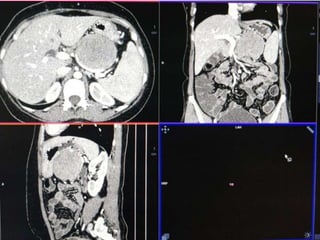

 55 yr old female patient

 Presented with complaints of lump abdomen and vague

abdominal discomfort

CASE 2

CASE2

DIFFERENTIALS

Diagnosis Points in favour Points against

Retroperitoneal

sarcomas

• Leiomyosarcoma

/Undifferentiated

Liposarcoma

• MFH

Age and clinical

presentation

Imaging features

(Large ill defined

heterogeneously

enhancing lesion

with areas of

necrosis)

No fat density/

calcification

No calcification

GIST Age

Biopsy:

 Poorly differentiated Leiomyosarcoma